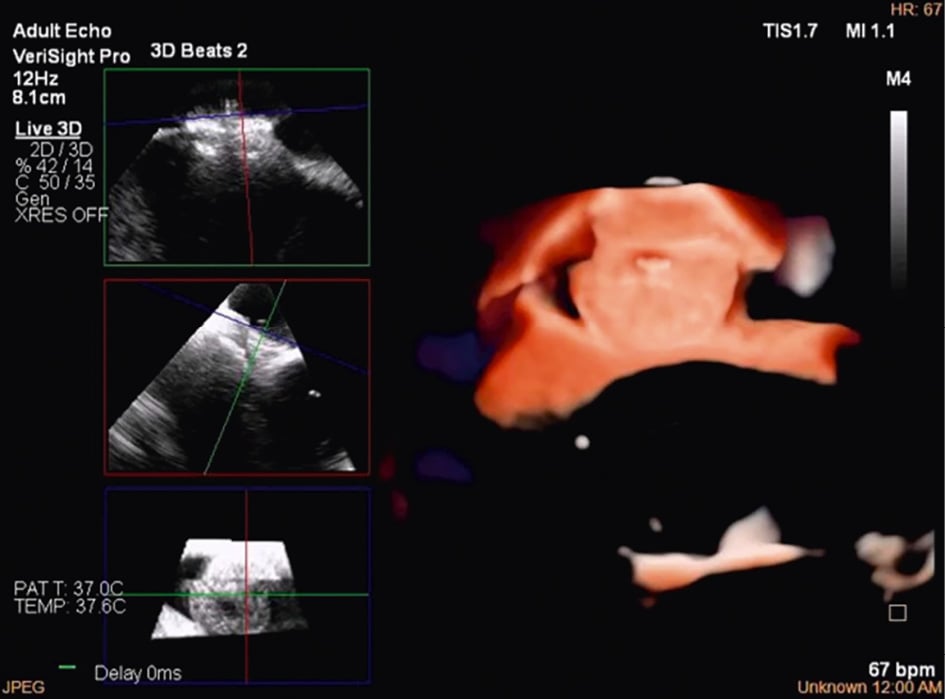

Although PFO/ASD procedures can be performed using a simple 2D ICE probe, in some more challenging anatomical settings (e.g., floppy interatrial septum [IAS], doubt about PFO/small ASD, particular PFO tunnel), 3D ICE can be of added value. When 3D ICE is used for PFO or ASD procedures, positioning within the right atrium is sufficient. With 3D ICE, the septal defect can be visualised in a 3D volume and typically only a catheter position is needed. When starting the procedure, the operator should screen patients for additional septal defects that may have been missed on the preprocedural imaging and determine whether there is a floppy interatrial septum (for PFO) and a sufficient superior and inferior rim (for ASD). Three-dimensional ICE allows us to determine the size of the septal defect (especially for an ASD closure), guide occluder deployment, verify placement post-deployment, and screen for residual shunts1 (Figure 12, Figure 13, Moving image 18-Moving image 19-Moving image 20-Moving image 21-Moving image 22).

Figure 12. Three-dimensional ICE-guided patent foramen ovale closure. A) 2D imaging allowing assessment of needle tenting in the middle of the fossa ovalis. B) Biplane imaging allowing assessment of the catheter after crossing the septum in the superior-inferior and anterior-posterior positions simultaneously. C) 3D multiplanar reconstruction (MPR) allowing assessment of the catheter after crossing the septum. D) 2D imaging showing the deployment of the right disc of the device. E) 3D MPR allowing simultaneous assessment in the lateral, axial, and azimuthal planes of the right disc of the device. F) 3D reconstruction of the device. 2D: two-dimensional; 3D: three-dimensional; ICE: intracardiac echocardiography

Figure 13. Three-dimensional multiplanar reconstruction views of the device in the interatrial septum.